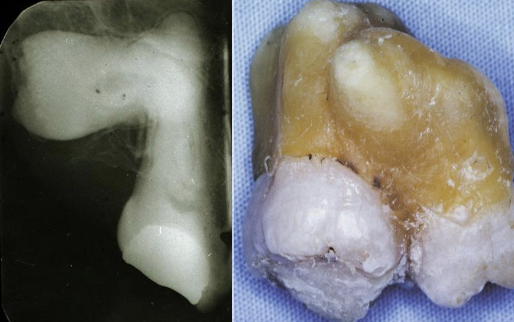

deep surface enamel invagination of the crown or root “tooth within tooth”; can be coronal (most frequent) or radicular

dens invaginatus “dens in dente”

“dens in dente” type I

invagination is confined to the crown

“dens in dente” type II

invagination extends below the CEJ

“dens in dente” type III

invagination may extend through the root

what is the dx?

dense invaginatus